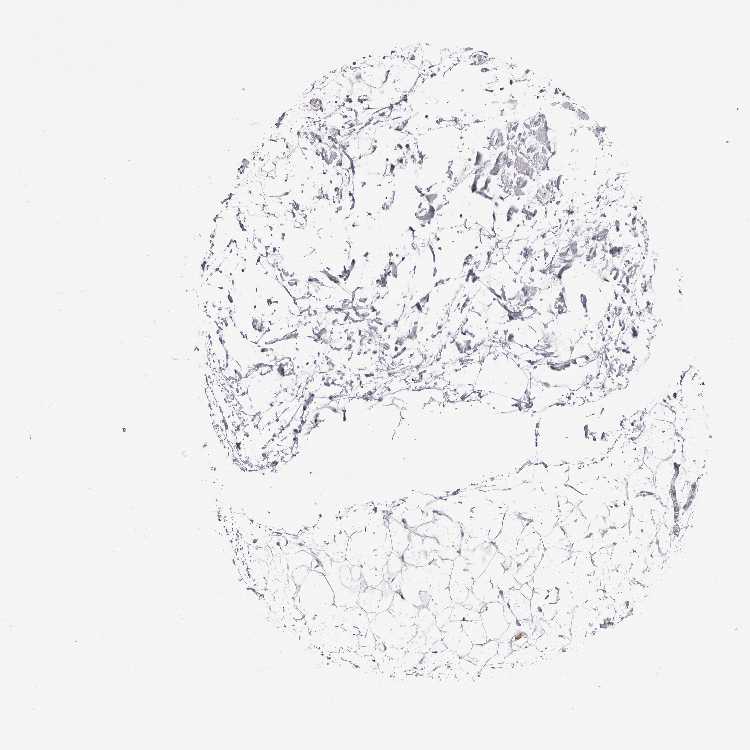

TISSUE PRIMARY DATA SOFT TISSUE Show tissue menu

SOFT TISSUE - Expression summary

SOFT TISSUE 1 - Antibody stainingi

Antibody staining in the annotated cell types in the current human tissue is reported as not detected, low, medium, or high, based on conventional immunohistochemistry profiling in selected tissues. This score is based on the combination of the staining intensity and fraction of stained cells.

Each image is clickable and will lead to virtual microscopy that enables deeper exploration of all samples and also displays staining intensity scores, fraction scores and subcellular localization as well as patient and tissue information for each sample.

Antibody HPA026918Antibody CAB013274Antibody CAB018389

Chondrocytes Not detected--

Fibroblasts Not detectedMediumHigh

Peripheral nerve -MediumMedium